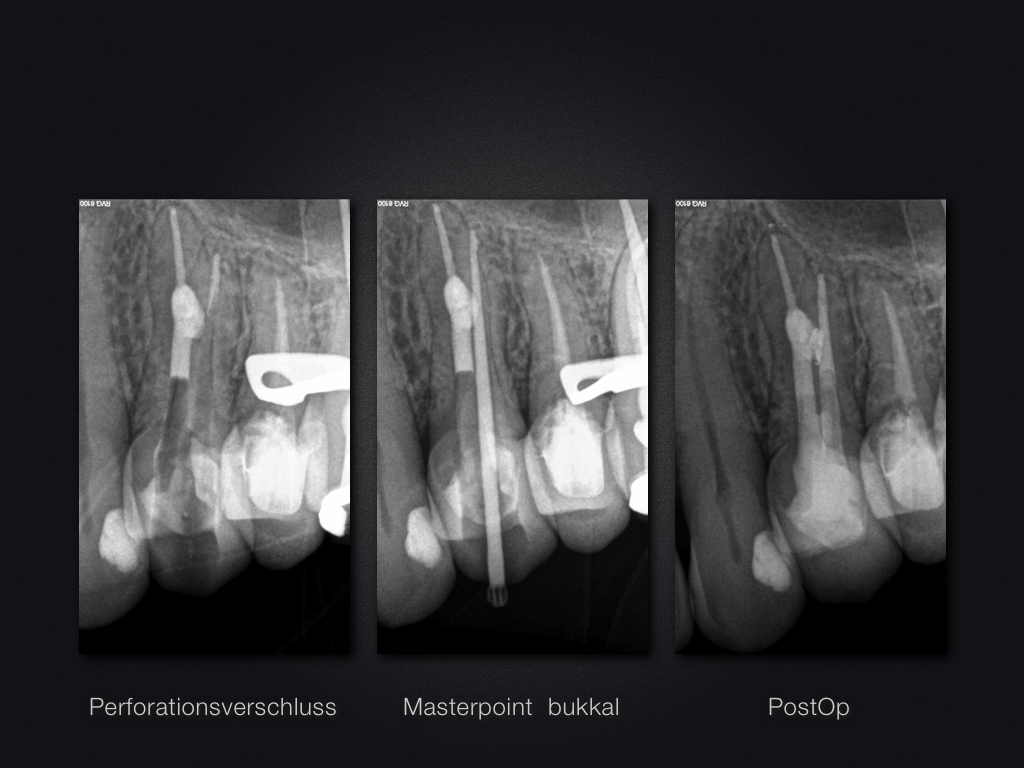

Perforationsverschluss im Kompromiss